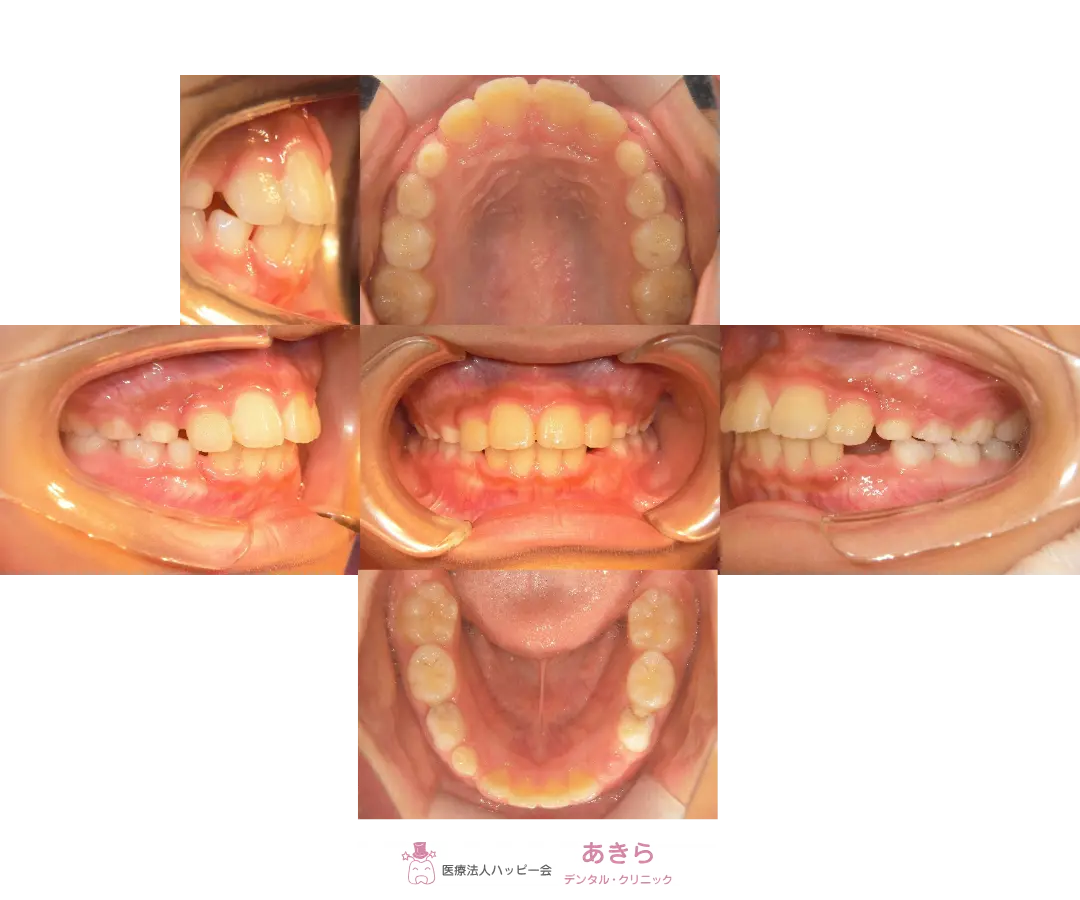

2023年4月12日 初診時口腔内写真(2023年5月 ハビットコレクタースタート)

2024年10月29日 経過 口腔内写真